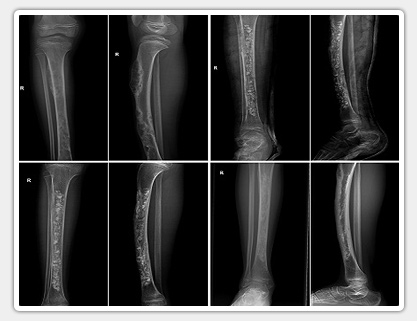

Synthetic Bone Substitute